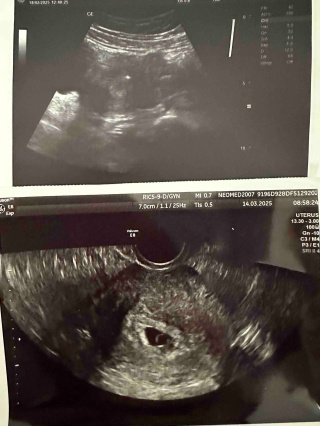

7 лютого 2025 року відбулося довгоочікуване перенесення ембріонів. Вже 19 лютого аналізи вперше підтвердили вагітність. А 3 березня контрольне ультразвукове дослідження показало найцінніше життєздатний, бажаний, омріяний малюк.